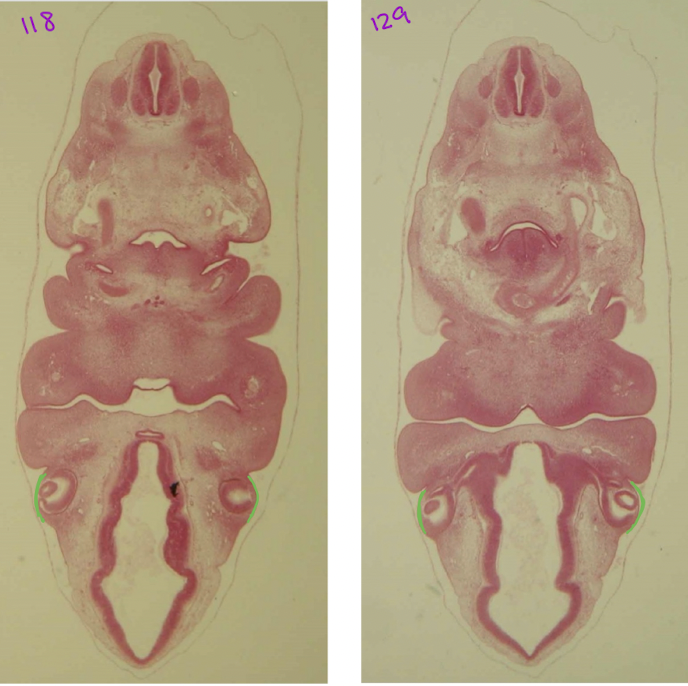

green: dorsal pancreas orange: ventral pancreas